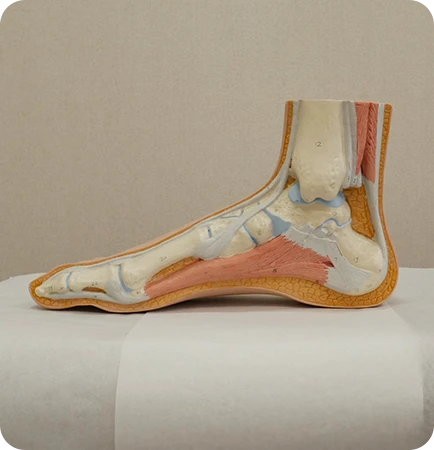

발 모양에 따라

▲ 평발

▲ 요족

▲ 정상발

평발형 오다리

요족형 오다리

평발형 엑스다리

요족형 엑스다리

X다리 일 때,

평발인 경우가 많음

휜다리는 발과 다리의 교정뿐 만아니라 골반과 척추의 밸런스를 맞춰야하는데 이때 가장 필요한 것이 족부 교정입니다.

발과 발목의 변형을 교정할 필요가 없는 휜다리는 흔치 않으며 발을 교정해야 교정후 재발 걱정이 없습니다.

족부교정

맞춤형 깔창을 통해 평발과 요족 등

발의 변형을 바로 잡아

하지의 회전을 최소화

무너진 아치 바로잡기

휜 발목 바로잡기